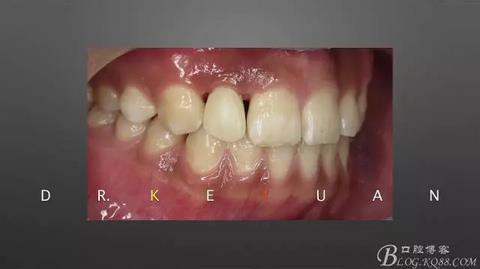

CASE 3—16歲少年外傷后一周來(lái)診,RCT后纖維樁及樹脂功能恢復(fù)

360截圖20170120135051661.jpg

一個(gè)牙髓壞死,一個(gè)活髓,首先一次性根管治療